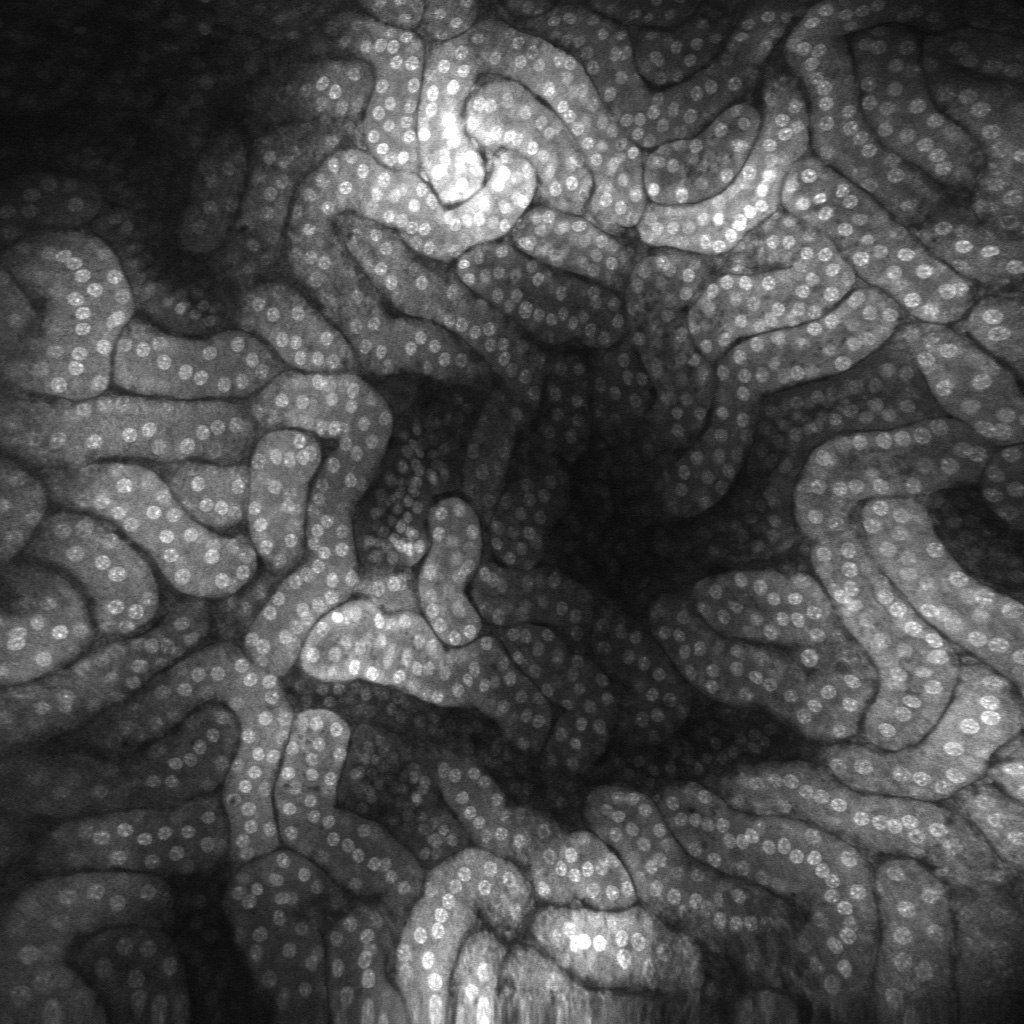

Superb resolution Using a distal end single scanning fibre rather than a proximally placed scanning fibre bundle provides unmatched lateral and axial resolution. The single fibre eliminates dead spaces and broken fibres, delivering high sensitivity and long lifespan. |

Users can generate images at the single-cell level, in real-time. - Viewing live biological systems in-vivo at the cellular level in their entirety

Easy to work on live tissues. - Image depth variation

Images can be easily post-processed to produce a range of presentations (incl 3D).